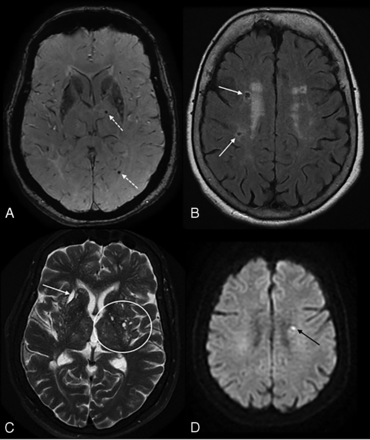

A, Recent subcortical infarct in the right lentiform nucleus in a 59-year-old woman with a history of hypertension. From left to right, axial DWI, ADC map, FLAIR, and coronal T2WI show restricted diffusion (solid white arrow, A). On coronal T2WI, the elongated morphology of the acute infarct in the craniocaudal axis (dashed white arrow, A) is related to the territory of a perforating artery. B, A lacune of presumed vascular origin in a 67-year-old man with a history of dementia. From left to right, axial DWI, T2WI, FLAIR, and T1WI show a remote lacunar infarct in the left frontal corona radiata, which demonstrates T2 hyperintensity with a peripheral rim of gliosis, best seen on FLAIR image (solid white arrow, B). C, Prominent perivascular spaces in a 63-year-old man with a history of dementia. A prominent perivascular space is noted in the left insular region with a centrally traversing vessel (solid white arrow, C), without peripheral gliosis on the FLAIR image (dashed arrow, C). Additionally, there are >20 dilated perivascular spaces in the bilateral basal ganglia on axial T2WI (circles, C). D, Cerebral microbleeds with cSS in an 87-year-old man with a history of CAA who presented with a worsening mental status. Axial SWI demonstrate multiple foci of susceptibility artifacts predominantly involving the basal ganglia and thalami, consistent with microbleeds. Additional areas of scattered cortical subarachnoid hemorrhagic staining (arrows, D) indicate cortical superficial siderosis.

According to the STRIVE criteria, the term “recent small subcortical infarcts” refers to a recent infarct occurring in the territory of a perforating arteriole with symptoms or imaging features that suggest a timeline of a previous few weeks. However, in most patients, these lesions can appear without apparent clinical symptoms (silent infarcts) (Online Supplemental Data).11 The term “recent” is preferred instead of “acute” because it includes both the hyperacute stage and the first few weeks of the lesion.11 These lesions typically measure ≤20 mm in their maximum diameter in the axial plane, though in the coronal plane, they can appear slightly larger and elongated, reflecting the territory of the occluded perforating arteriole (Fig 2A). They are best identified with hyperintense signal on DWI, hypointense signal on an ADC map, and hyperintense signal on T2-weighted and FLAIR sequences. The most common fate of these lesions on long-term follow-up is cavitation to become a lacune (in 28%–94%, depending on the duration of follow-up), turning into a nonspecific focus of T2/FLAIR hyperintensity, or eventually completely disappearing.2,8 Furthermore, STRIVE proposes that lesions in the basal ganglia and internal capsule of >20 mm are a different subtype and, therefore, should be classified as striatocapsular infarcts instead of small subcortical infarcts. Similarly, infarcts of the anterior choroidal artery are etiologically and anatomically distinct.

The STRIVE guidelines define lacunes of presumed vascular origin as round or ovoid, subcortical, fluid-filled cavities (with signal similar to that of CSF in all sequences), measuring between 3 and 15 mm in diameter, consistent with a previous, small subcortical infarct or hemorrhage located in deep gray and white matter and in a territory of perforating arteriole (Fig 2B and Online Supplemental Data). These lesions typically demonstrate a surrounding gliotic rim of T2 FLAIR hyperintensity (Figs 3 and 4), which can be a useful feature when present. A peripheral gliotic rim can also surround perivascular spaces when they pass through an area of white matter hyperintensity. Although lacunes are commonly seen in older patients without symptoms, they are associated with an increased risk of stroke, dementia, and gait impairment.5,11

Perivascular spaces are extensions of the extracerebral fluid space that are covered by the pia mater, which surrounds cerebral vessels from the brain surface into and through the brain parenchyma. These are commonly microscopic and not visible on conventional neuroimaging, but when they become prominent and numerous, they are considered a marker of SVD. PVS have been shown to be associated with other SVD markers such as WMH and lacunes, but not atrophy.11 PVS have a signal intensity similar to that of CSF in all sequences and appear round or ovoid with a diameter of <3 mm but can appear more elongated when imaged parallel to the course of the penetrating vessel. They are typically located in the inferior basal ganglia, centrum semiovale, and midbrain and do not have a surrounding gliotic rim (in contrast with lacunes) (Fig 2C and Online Supplemental Data). Although lacunes and PVS can have similar MR imaging features, pathologic studies have demonstrated that lesions that are <3 mm in diameter are more likely to be perivascular spaces than lacunes.11 A traversing vessel can sometimes be seen in the center of a perivascular space when imaged at high resolution, another differentiator of PVS versus lacunes (Fig 2C). The severity of PVS is typically assessed on axial T2-weighted images using a validated 4-point visual rating scale based on the total number of PVS (0 indicating no PVS; 1 [mild], ≤10 PVS; 2 [moderate], 11–20 PVS; 3 [moderate to severe], 21–40 PVS; and 4 [severe], >40 PVS) in the basal ganglia and centrum semiovale (Table 2).33 The topography of PVS can be a helpful characteristic of the underlying SVD type: PVS are likely associated with arteriolosclerosis when located in the basal ganglia, and they are more likely to be related to CAA when located in the centrum semiovale (Fig 4).10 However, the clinical significance of PVS remains unclear; a few studies have reported that PVS can be associated with an increased risk of dementia if located in the basal ganglia and white matter.5,10,36

CMB are small round or ovoid lesions (≤10 mm in diameter) of marked hypointensity with associated blooming on T2 gradient-echo (T2*) or other sequences that are sensitive to susceptibility effects, especially SWI (Fig 2D and Online Supplemental Data). CMB correspond to hemosiderin-laden macrophages in perivascular tissue, consistent with vascular leakage of blood cells.5 Several visual scores are available, including the Microbleed Anatomical Rating Scale and the Brain Observer MicroBleed Scales, which have reasonable intrarater and interrater reliability for the presence of definite microbleeds.37,38 In fact, a few recent publications have proposed a novel automatic method to detect CMB from MR images by exploiting the 3D convolutional neural network.39 CMB are associated with an increased risk of cognitive decline and ischemic and hemorrhagic stroke, though the risk of dementia appears higher in patients with CMB restricted to a superficial/lobar location compared with those with deep involvement.5,10 Two other hemorrhagic manifestations of SVD include cSS and spontaneous intracerebral hemorrhage (in contrast to secondary hemorrhage due to other causes such as trauma and vascular malformations).

High SVD burden in a 55-year-old man with a history of arterial hypertension. Note multiple microbleeds in the left thalamus and occipital lobe (dotted arrows) on SWI (A), remote lacunar infarcts in the right centrum semiovale (white arrows, B), and WMH Fazekas 2 on FLAIR (B). More than 20 dilated perivascular spaces are seen on axial T2WI (circle, C) and remote lacunar infarct in right lentiform nucleus (white arrow, C). The total SVD score is 4. The patient developed an acute lacunar infarct (black arrow) on DWI (D) 10 months later.